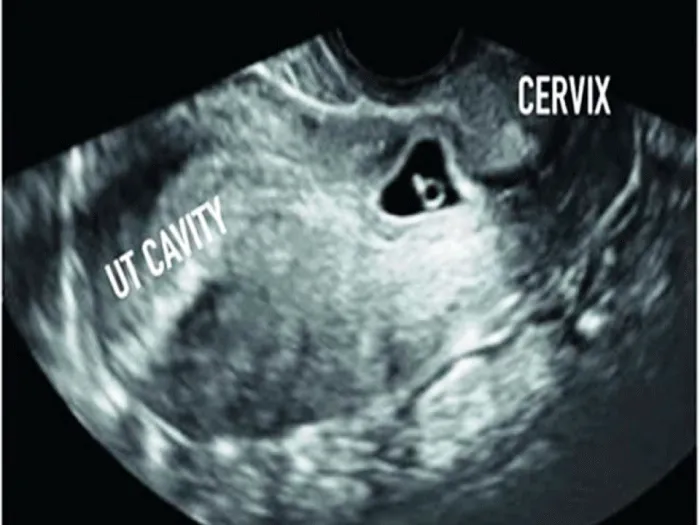

A 26 years old lady who had previously given birth to two children by cesarean sections (CS) and an exploratory laparotomy 10 years before marriage for removal of a complicated ovarian cyst. She was presented with a 2 weeks missed period where trans-vaginal ultrasound revealed a 5 weeks single intrauterine gestational sac equipping the isthmo-cervical portion of the uterus almost at site of the previous caesarean section scar with empty uterine cavity Figure 1. Two weeks later, the sac was still in the same site with positive fetal pulsation and another two weeks later, she started to develop mild vaginal bleeding with mild lower abdominal pain where ultrasound revealed healthy pregnancy with retro-chorionic hematoma 5 × 4 cm. 3 Dimension Ultrasound Doppler revealed the absence of demarcation line between trophoblast and myometrium with the trophoblast reaching as far as the serosa of the peritoneum covering the urinary bladder Figure 2. Termination of pregnancy by laparotomy was performed where the urinary bladder was found completely adherent to the uterus with high vascularity and varicosity covering this area. Bilateral uterine arteries ligation was done before opening the uterus. Small bladder injury occurred during dissection of the urinary bladder, which was sutured later on in double layer. On uterine incision, chorionic tissue was found bulging from site of the scar Figure 3 with a small part adherent to the uterine wall, excision of this part and closure of uterus was done after taking 3 U-shaped sutures in the lower part of the uterus. Patient received 2 units of blood and 2 units of plasma.

Placenta accreta (and percreta) are not commonly diagnosed in the first trimester. They are usually diagnosed with the massive bleeding encountered during dilatation and curettage secondary to myometrial invasion by the placenta, unfortunately, a retrospective diagnosis [3]. The suspicion of placenta accreta developed in this case as early as the first ultrasound done showing a low lying gestational sac with empty uterus [2].

This diagnosis of placenta accreta (PA) is difficult during the first trimester, the currently known prenatal sonographic characteristics of PA low-lying gestational sac with diffuse dilatation of intra-placental vessels (lacunae). Also, PA is suspected if part of the lining of the gestational sac is embedded in the previous CS scar with an irregular decidual layer and thinning of the underlying uterine wall [5,6].